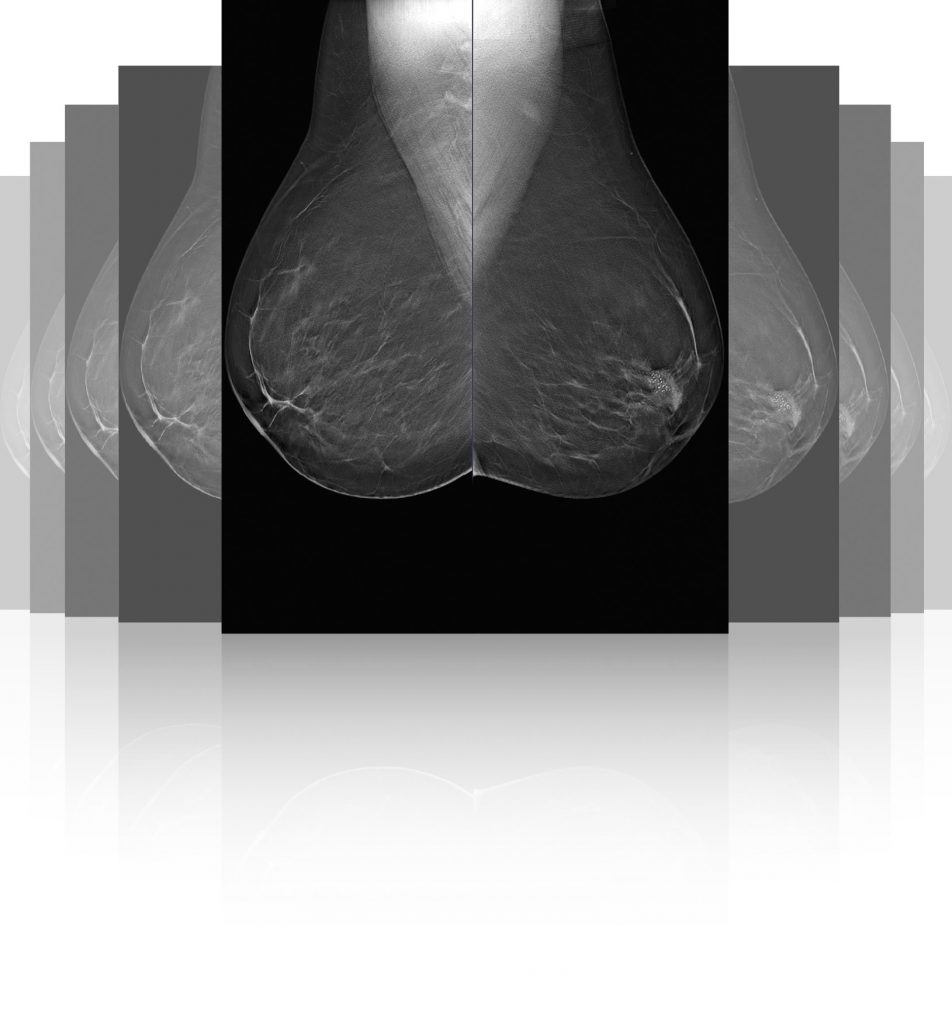

Digital Mammography with the most reliable digital mammography systems

MEDICAL SYSTEMS P.C. markets mammography systems of well-known foreign firms and equips diagnostic and medical centers, clinics and hospitals.We are beside you from the stage of research and study on the appropriate mammography system, supply, installation and maintenance over time.